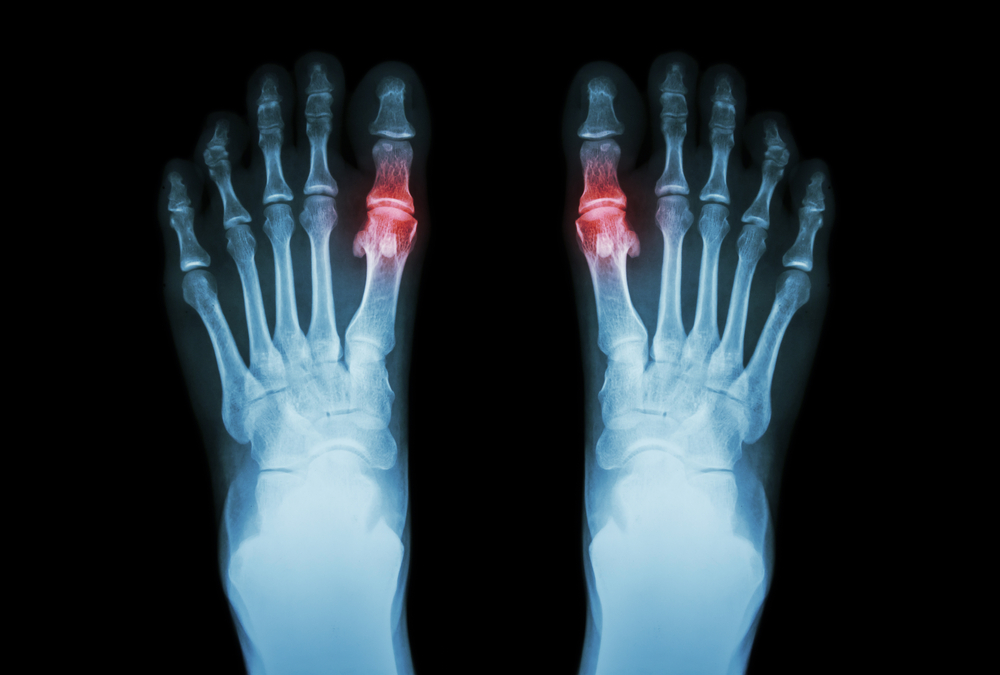

Why Do Bunions Get Worse Over Time?

Bunions, also called Hallux valgus, are often painful protrusions at the bottom of your big toe. They can cause a wide range of issues such as bursitis, hammertoe, and metatarsalgia, which is why you should contact your local Victoria, Kelowna, or Nanaimo foot...